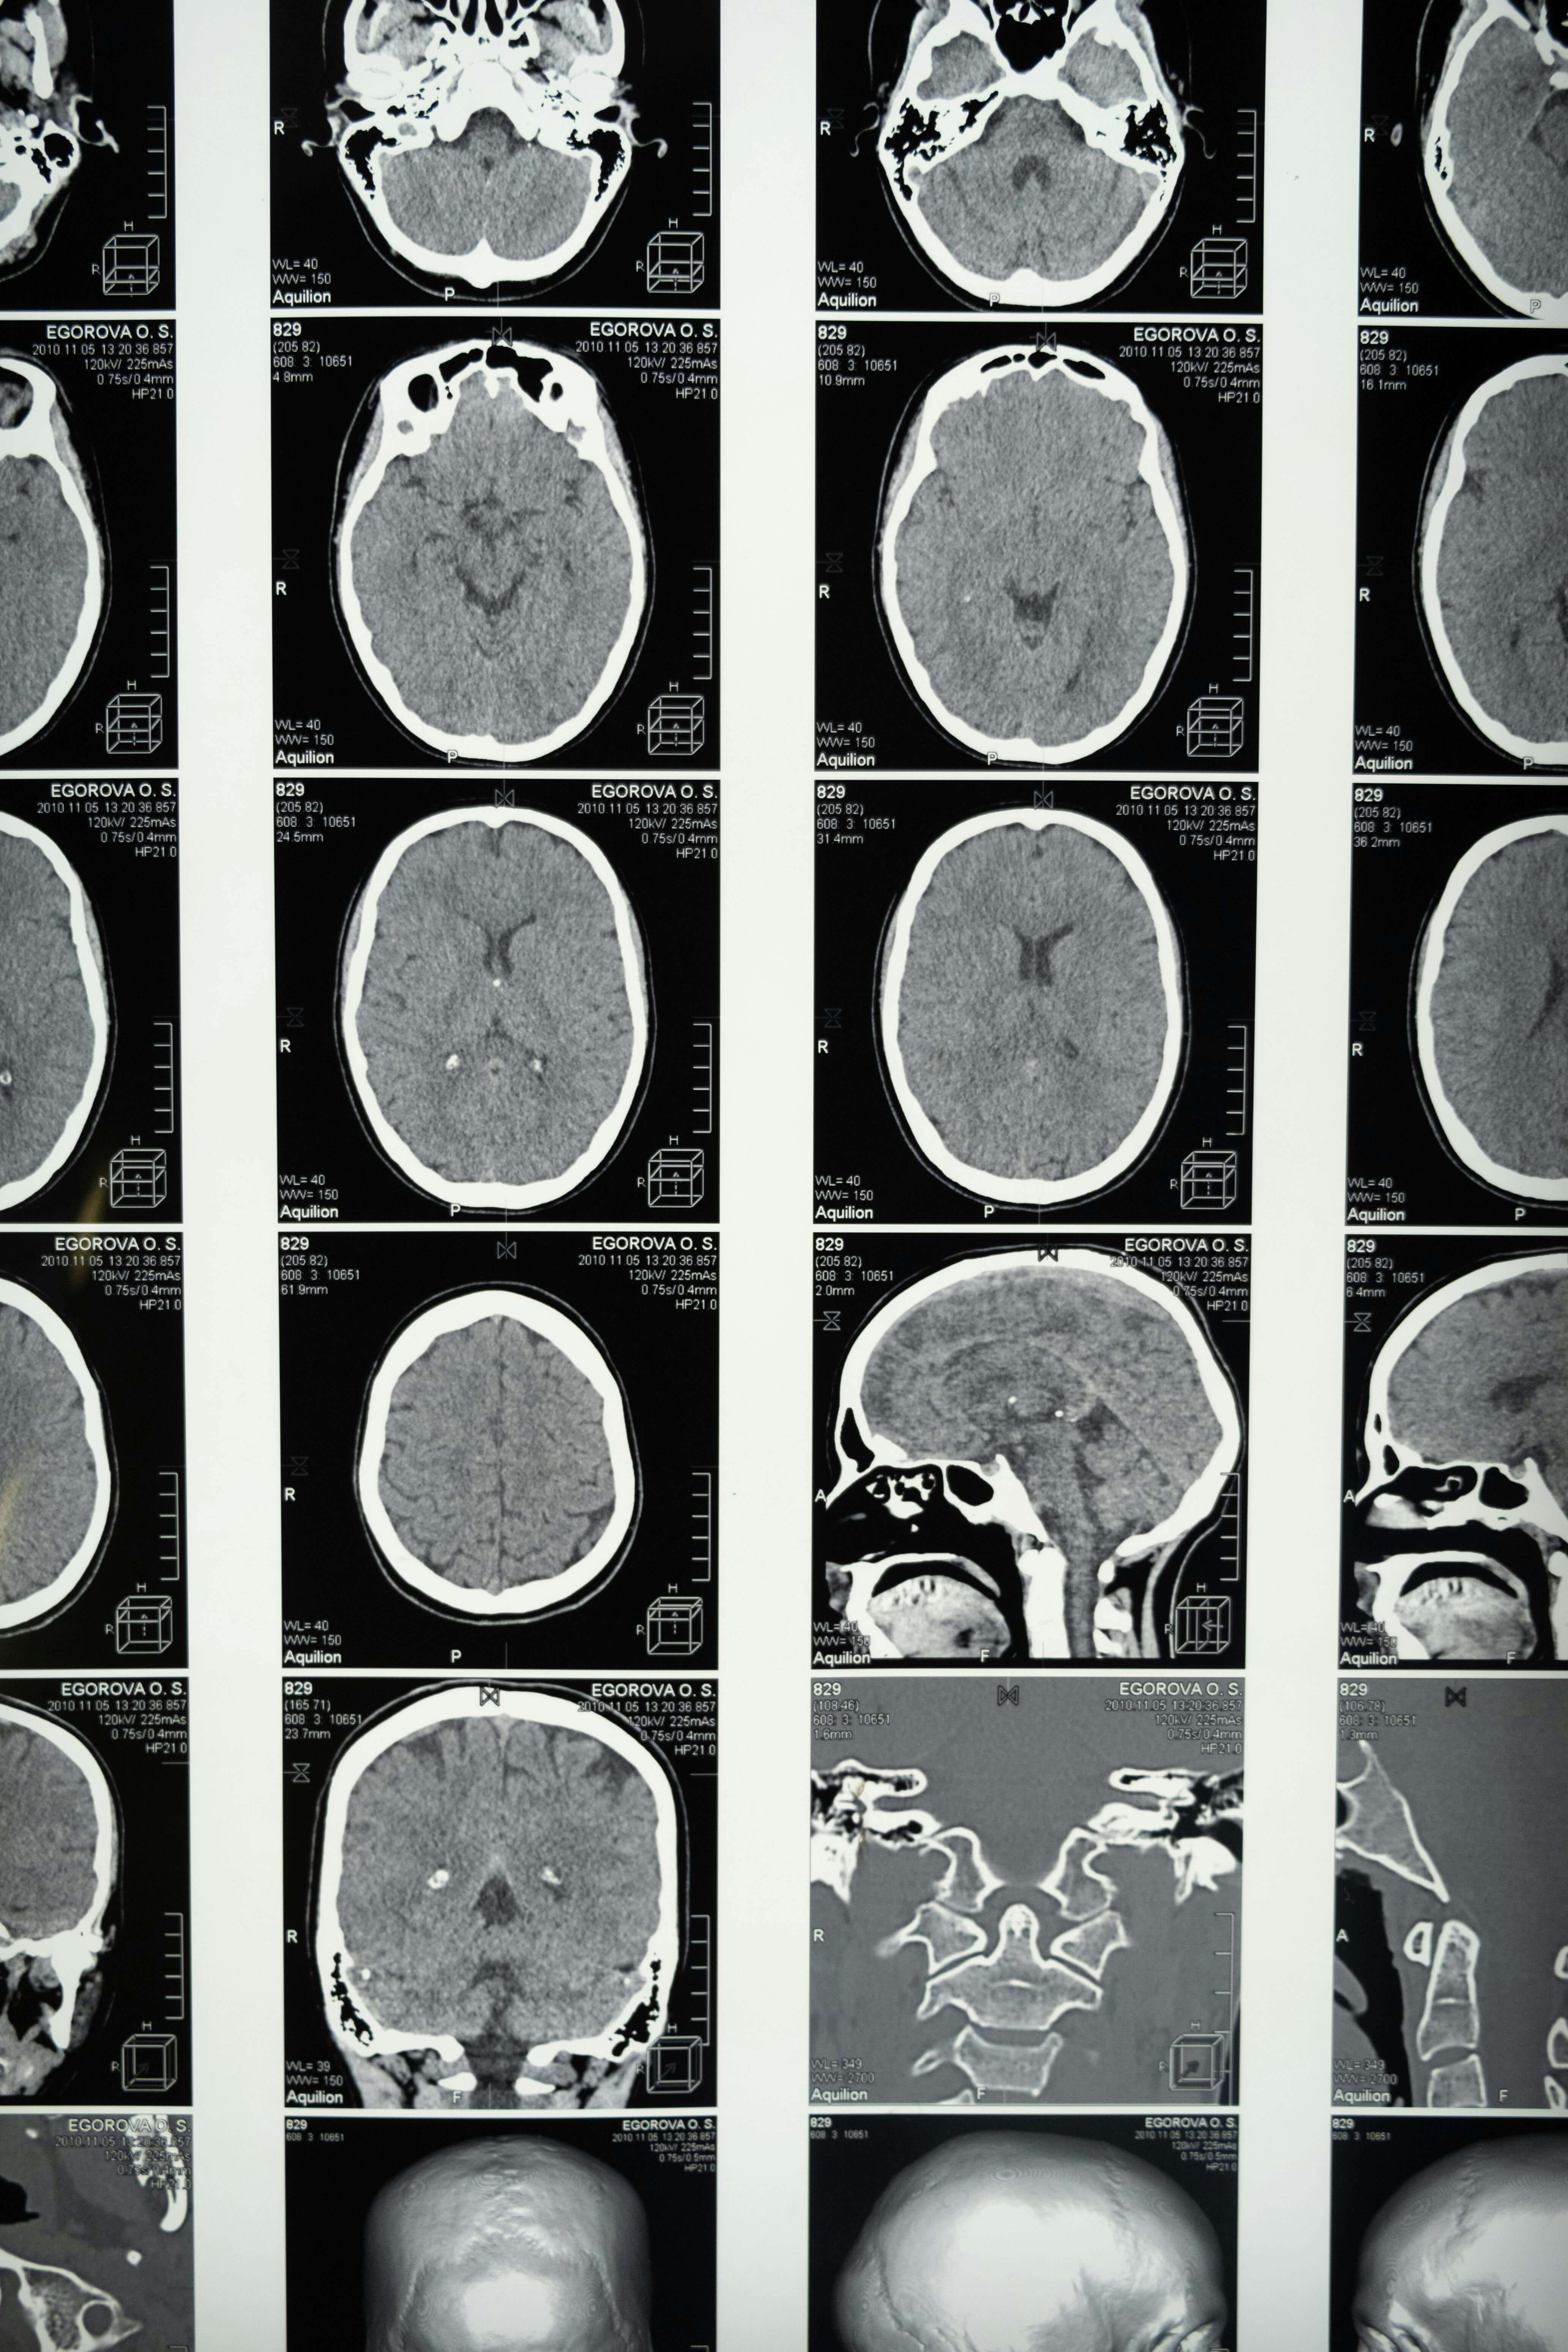

외상성 뇌 손상(Traumatic Brain Injury, TBI)은 갑작스러운 외부 충격으로 인해 뇌 기능이 손상되는 상황을 말합니다. 최근의 연구 결과는 TBI가 뇌졸중과 같은 심각한 혈관 질환의 위험을 증가시킬 수 있음을 시사합니다. 미국심장협회지에 발표된 연구에 따르면, TBI를 경험한 사람은 그렇지 않은 사람에 비해 뇌졸중의 발생 확률이 1.9배로 증가한다고 보고되었습니다. 이 연구는 특히 50세 미만의 성인이 TBI로 인해 장기적인 건강 위험에 노출될 수 있음을 보여줍니다.

따라서 외상성 뇌 손상을 입은 사람들은 뇌졸중 예방을 위한 특별한 조치를 고려해야 합니다. 뇌졸중은 뇌에 혈액 공급이 중단되거나 출혈이 발생하여 뇌 손상을 초래하는 질환으로, 조기 발견과 처치가 중요합니다. 외상성 뇌 손상의 이력이 있는 환자는 정기적인 건강 검진과 적절한 건강 관리가 필수적입니다.